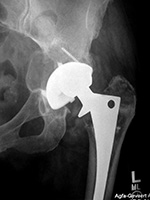

Osteolysis and particle disease in right hip implant

There is displacement of the right acetabular implant component and osteolysis from granulomatous particle disease. A left metal upon metal hip implant is present.